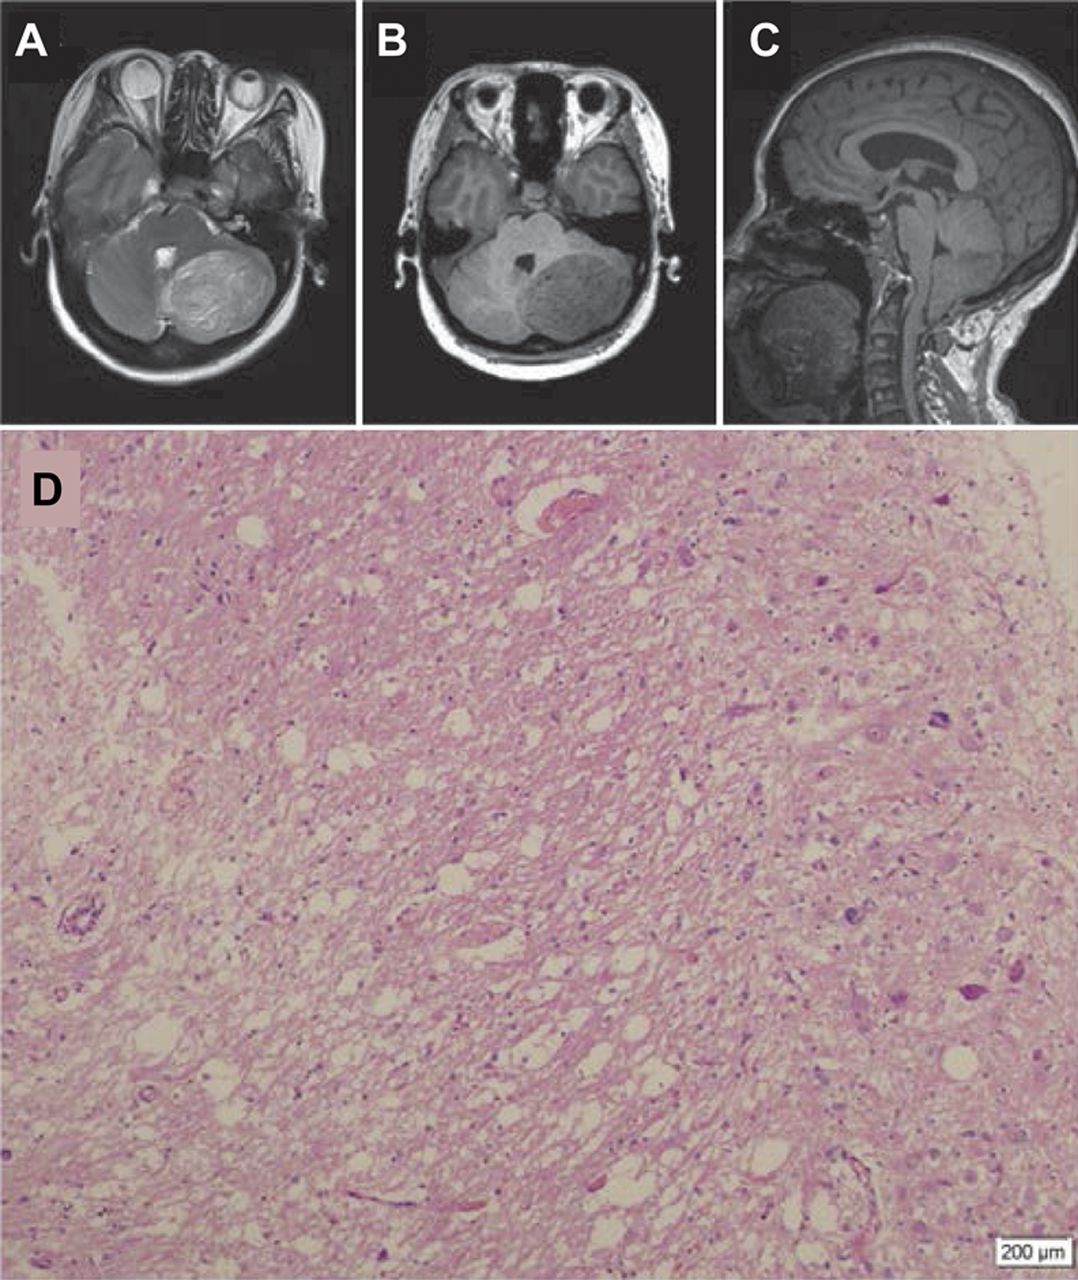

一名48岁的女性因三年历史的间歇性头晕和不稳定的步态。头颅MRI T2 hyperintensity演示了一个夹层病变和T1 hypointensity涉及左侧小脑半球,出现放大(图中,得了)。二次脑积水和观察我畸形。因为有条纹的出现在MRI是Lhermitte-Duclos疾病的特点,1那些将要动手术诊断。执行全部切除的病变,病理评估确认诊断(图D)。后续neuroradiologic研究显示没有复发。然而,最近超声显示多个结节患者的右乳房,这是自信的预测Cowden疾病的临床诊断。2

MRI表现与病理组织检查

轴向T2和t1加权磁共振(A, B)显示,典型的有条纹的模式与交替乐队Lhermitte-Duclos疾病特征。温和脑积水和下级流离失所的小脑扁桃体在矢状t1加权图像(C)指出。病理研究(D)(苏木精和伊红染色;比例尺= 200μm)证实了MRI诊断。